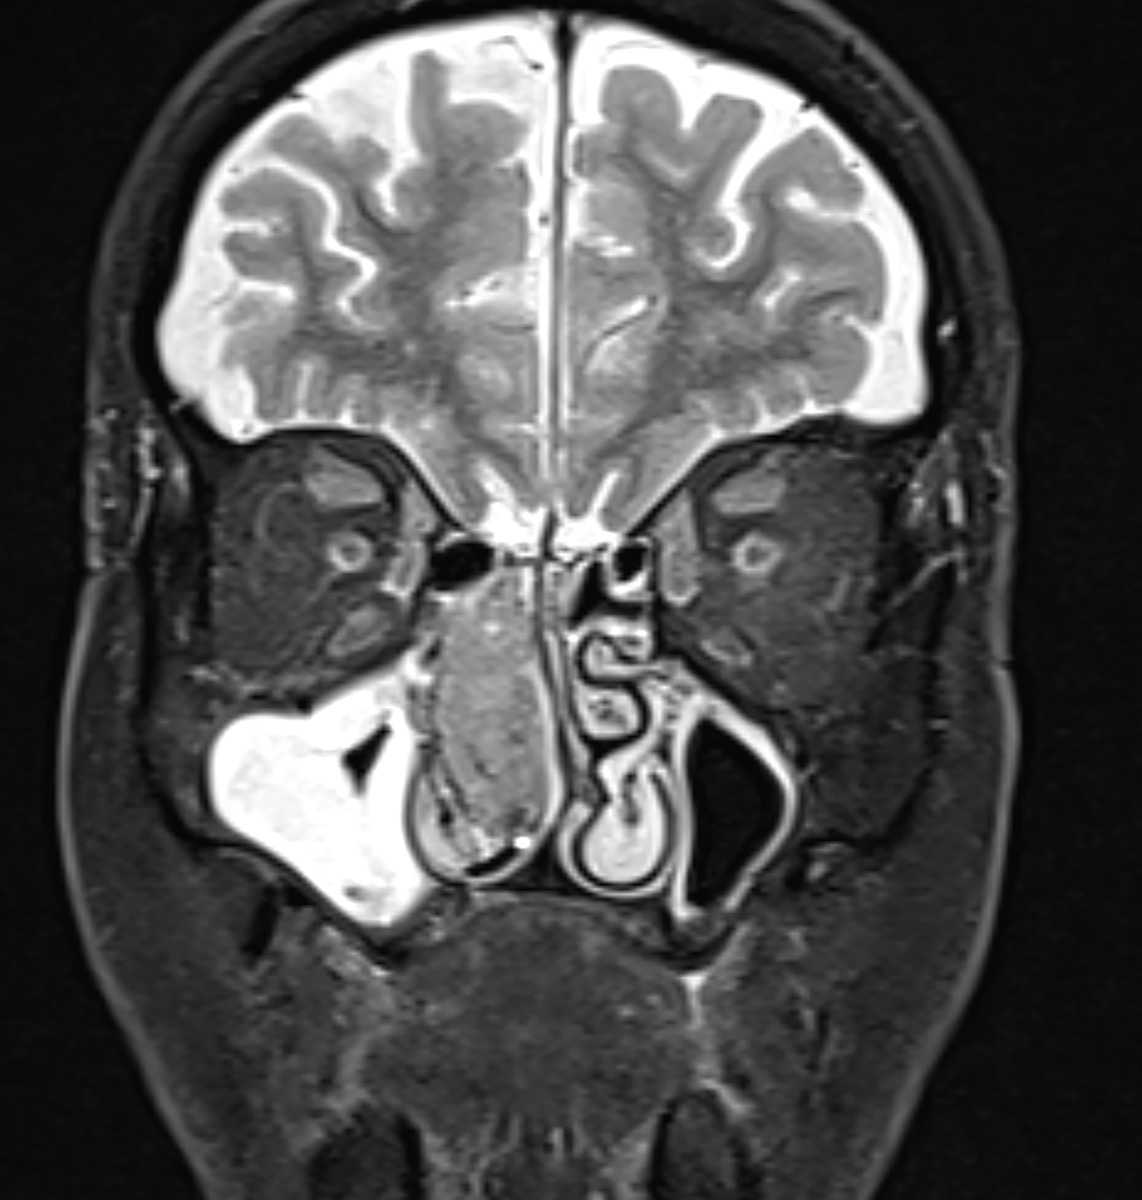

Molecular and Genomic Profiling of Head and Neck Tumors

- PI: Richard V. Smith, MD

- Sponsor: Montefiore Einstein